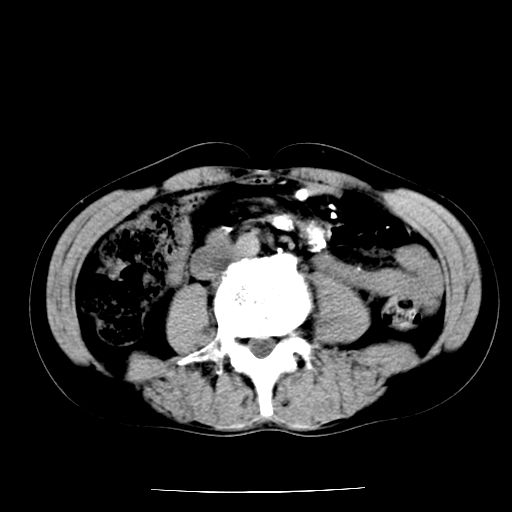

男,59岁,“结核性胸膜炎”30余年,胸部经常疼痛,多次x检查提示“肺部”炎症。腹部疼痛5日,b超提示:“肝内短管结石,余显示不清,建议进一步检查。”

两肺结核并右侧胸腔积液;脾脏、腹腔及腹膜后淋巴结结核[陈旧性];肝内胆管结石

胸部腹部都是结核(双肺。纵隔淋巴结,肝脏,脾脏,肠系膜)

两肺结核并右侧胸腔积液;脾脏、腹腔及腹膜后淋巴结结核[陈旧性];肝内胆管结石。直肠息肉?